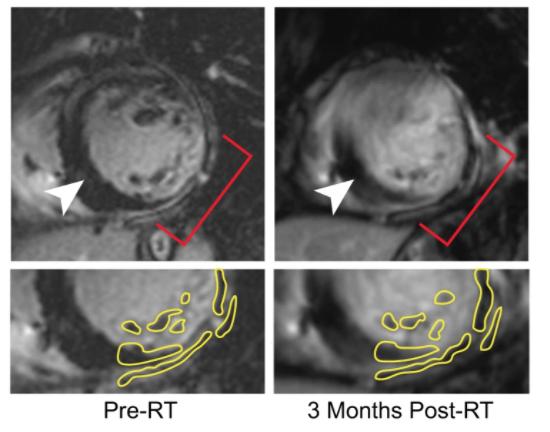

Radiology plays a crucial role in diagnosing — from guiding patients into the right treatment plans through follow-up ...